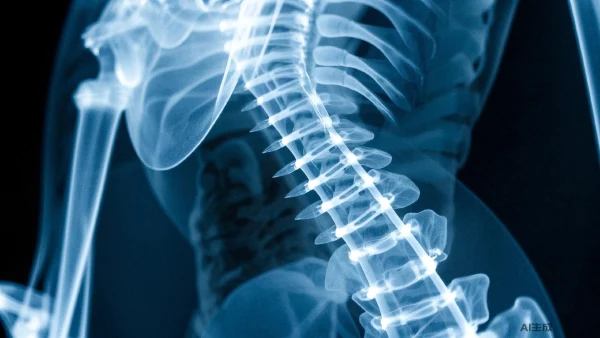

脊柱骨折可分为多种类型,包括腰椎骨折、胸椎骨折、颈椎骨折等。此外,不同的致病原因和临床表现也决定了其治疗方法的多样性。明确诊断脊柱骨折对治疗方案的选择至关重要。

脊柱骨折根据不同的标准可分为多种类型。按解剖部位分,可以分为颈椎骨折、胸椎骨折和腰椎骨折。按损伤机制分,可以分为挤压型骨折、爆裂型骨折和屈曲分离型骨折等。

影像学检查是诊断脊柱骨折的重要手段,包括X线、CT和MRI等。其中CT可以更清晰地显示骨折线和骨折碎片的排列情况,对手术方案的制定具有重要参考价值。